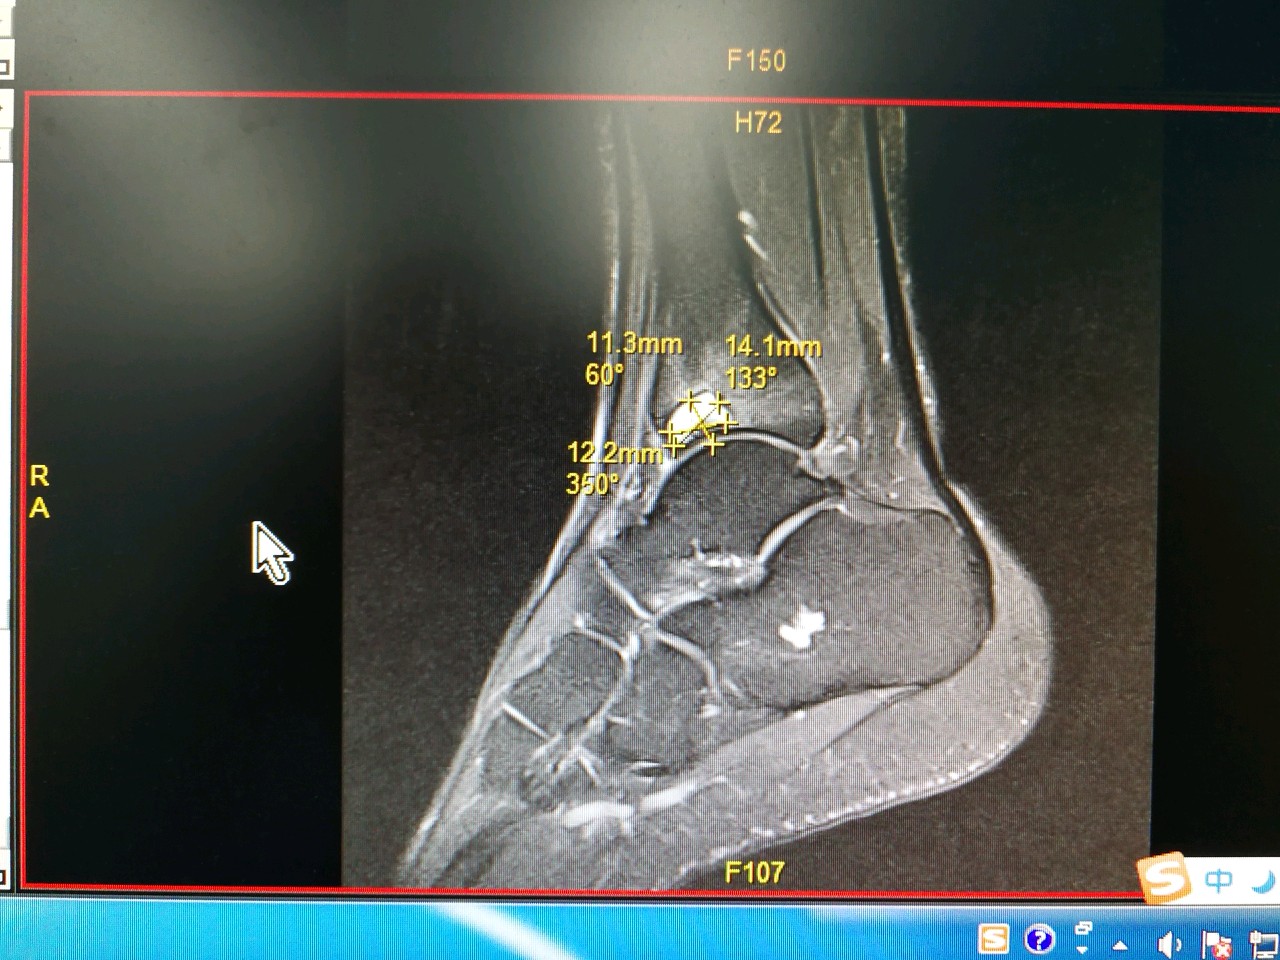

我们从发生在前两周的一个病例说起。那是我每周四的普通门诊,一个22岁的年轻小伙,一瘸一拐的走了进来,第一句话就是:医生我脚又崴了。这种主诉对我而言已经习以为常,但是,他接下来的话让我对他的病情感到担忧。他告诉我,在5年前打篮球时第一次扭伤踝关节,当时并没有去看医生,只是在家休养几天,自认为痊愈之后,继续进行高强度篮球运动。但是,平时运动后总会感踝关节疼痛不适,最重要的是他自己都不记得后面再次崴伤过多少次。经过详细的查体和影像学检查,印证了我的担忧。他的踝关节外侧副韧带撕裂,严重骨质增生,最致命的是踝关节软骨大面积重度损伤。通俗而言就是我们称之的关节退变。不可想象一个刚步入才花样年华的小伙,踝关节却以进入古稀之年。数年后面对他的很可能是踝关节融合或者关节置换。这就是实实在在的例子,它告诉我们:请关爱自己的脚踝。